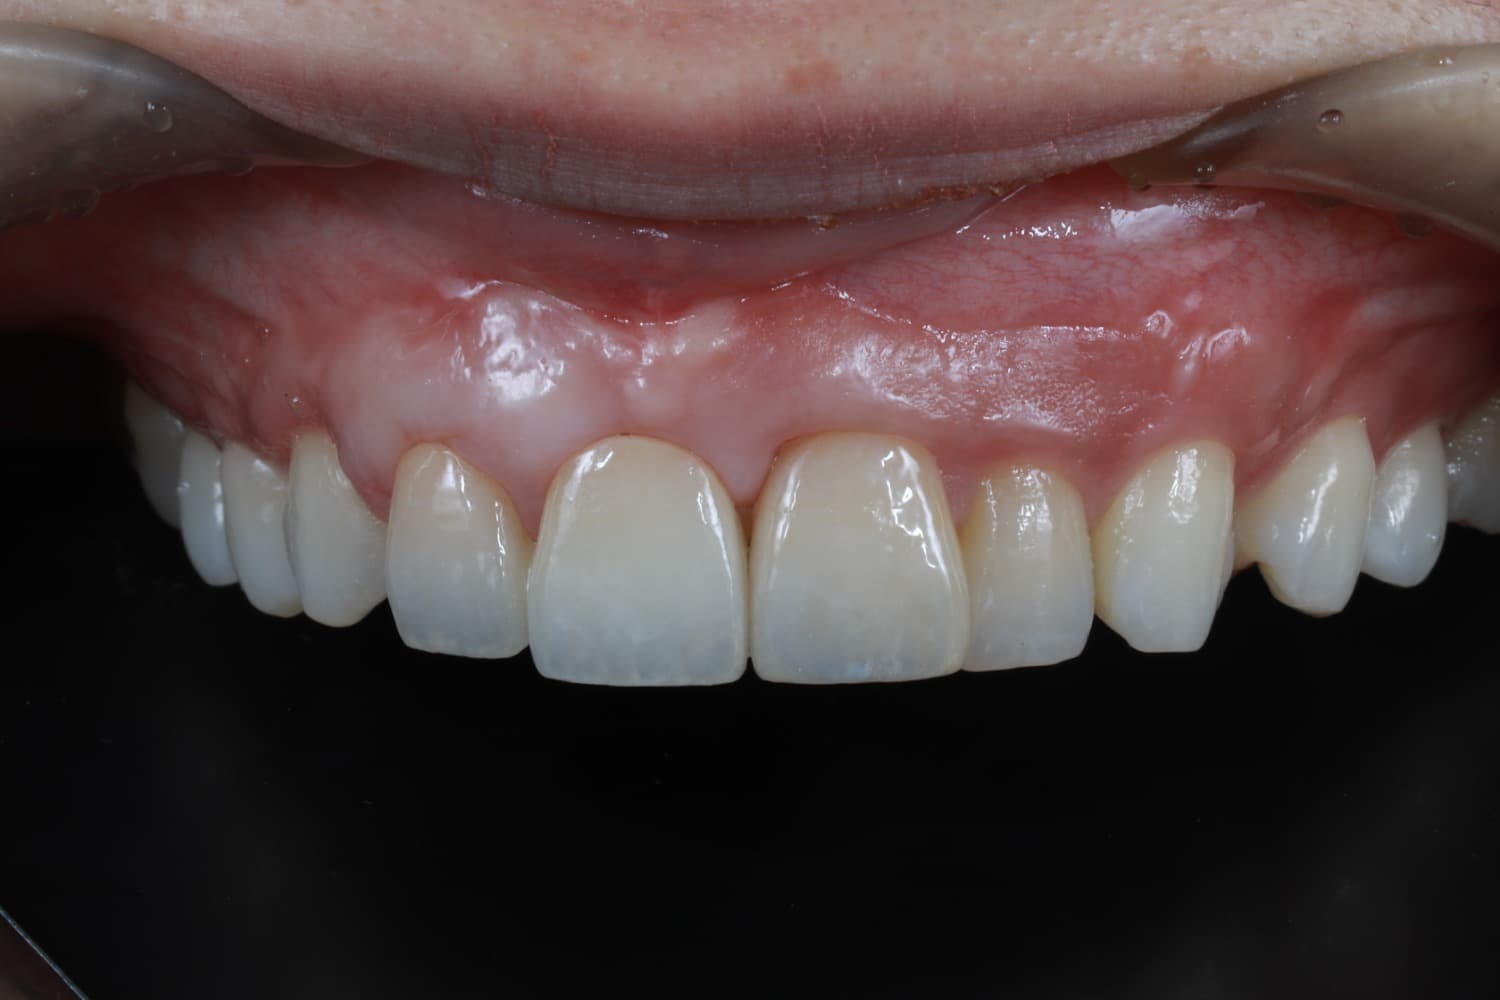

左上1のインプラント治療

Before

After

保存不可能な左上1を抜歯して、インプラント治療を行った 今回は歯間乳頭を作るために部分矯正も行う GBRやCTGも含む

年齢

30代

性別

女性

主訴

前歯が長くなってきた

治療期間

2年

治療回数

20回

費用

120万円

副作用・リスク

腫脹、疼痛